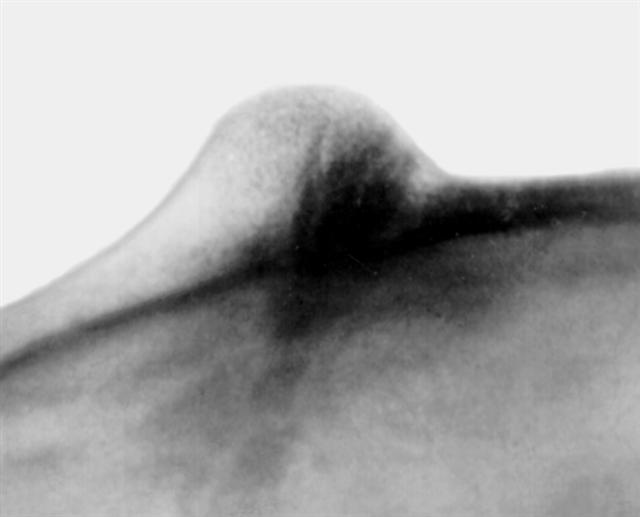

Рис. 5б). Рентгенограмма черепа больного при компактной остеоме теменно-височной области: прицельная (тангенциальная) рентгенограмма черепа, на которой видна структура компактной остеомы, расположенной в губчатом слое кости и наружной костной пластинке.